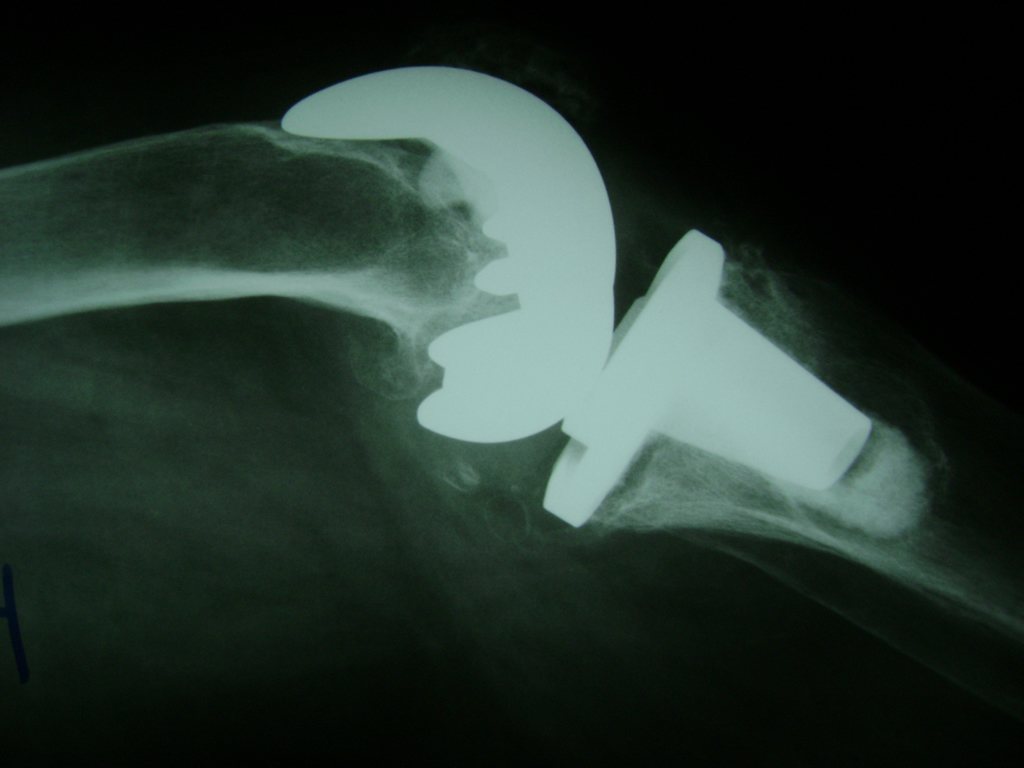

Cirugías de Húmero - Rodilla

La artroscopia de rodilla es un cirugía en el cual la estructura interna de la articulación es examinada ya sea para realizar un diagnostico o para realizar un tratamiento, este procedimiento se realiza utilizando un instrumento parecido a un pequeño tubo llamado artroscopio.